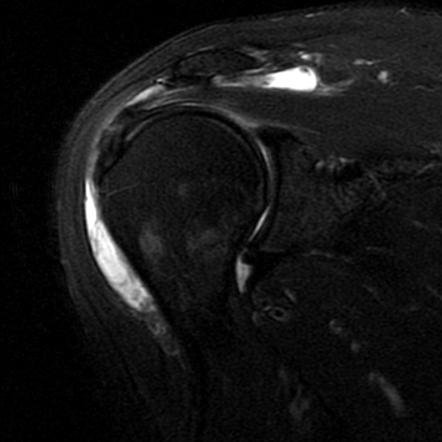

Imaging such as X-rays may be used to check for bone spurs or structural narrowing. Ultrasound or MRI can help confirm inflammation of the bursa, detect fluid buildup, and identify any coexisting rotator cuff tears.